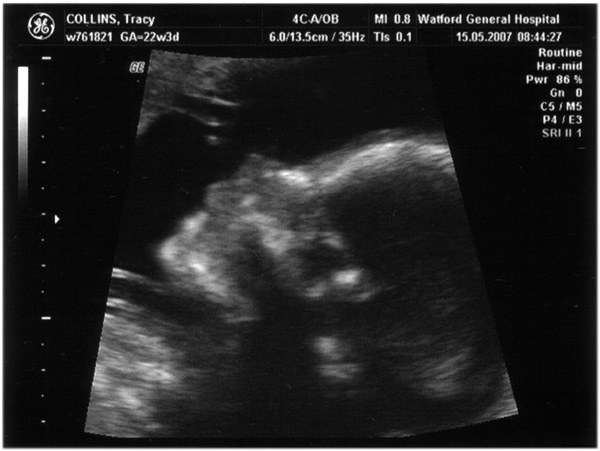

Third scan, 15th May 2007, (21 weeks)